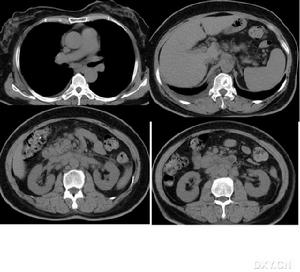

體檢常發現對稱、可活動、有彈性的淋巴結,大小為0.5-2cm,常無疼痛及觸痛。最常涉及的淋巴結為頸前、頸後、頜下、枕及腋窩淋巴結,肱骨內上髁及股淋巴結也可腫大,縱隔及肺門淋巴結也可受累,腹部CT常發現腸系膜及腹膜後淋巴結腫大。

3、影像學檢查頸部CT掃描除可了解腫瘤部位、範圍外,並有助於明確腫塊與頸動脈、頸內靜脈等重要結構的關係,為手術治療提供重要參考依據,但較小之腫塊,常不能顯影。為查找原發病灶,可酌情作鼻竇、鼻咽和喉側位等X線拍片檢查。對於頸部鰓裂瘺管或甲狀舌管瘺管,可行碘油造影X線拍片檢查,以了解瘺管走向和範圍。